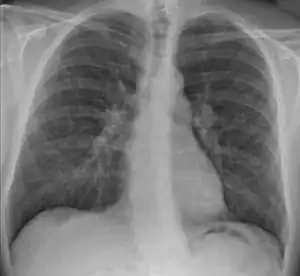

![]() | |

| 胸部 X 片顯示結節病的典型結節,主要位於肺門部位。 | |

許多情況下,結節病會造成肺部的病變,包括肺容量的減少,順應性(肺泡伸展的能力)的下降。因此,異常的胸部X線表現,往往是結節病的首要發現。人們往往通過胸部X線來做出初步診斷或者評估肺部病變的嚴重程度。

中華人民共和國的醫學資料中將胸部X線的改變分為五期,以Ⅰ期和Ⅱ期較為常見:[58]

- 0 期:肺部X線檢查陰性,肺部清晰無明顯的病變。

- Ⅰ期:兩側肺門和/或縱隔淋巴結腫大,右主支氣管旁淋巴結常常伴有腫大,而肺內無明顯異常。

- Ⅱ期:肺門淋巴結的腫大,伴肺浸潤影。

- Ⅲ期:可見肺部浸潤影,並無肺門淋巴結腫大。

- Ⅳ期:肺內發生纖維化、肺大皰和肺囊腫等改變。

以上分類僅僅是相對而言的,並不能說明一定會有0期-Ⅳ期的病變,可以是跳躍式發展。CT掃描(尤其是HRCT)能夠更準確地估計結節病的類型、肺間質的病變程度與淋巴結的腫大情況。[58]